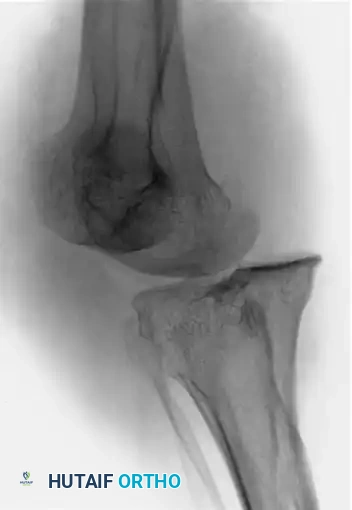

Initial radiographs demonstrated a severe posteromedial dislocation of the tibia relative to the femur, accompanied by a medial dislocation of the patella.

Figures A and B: Anteroposterior and lateral radiographs of the knee showing a posteromedial knee dislocation with medial dislocation of the patella.